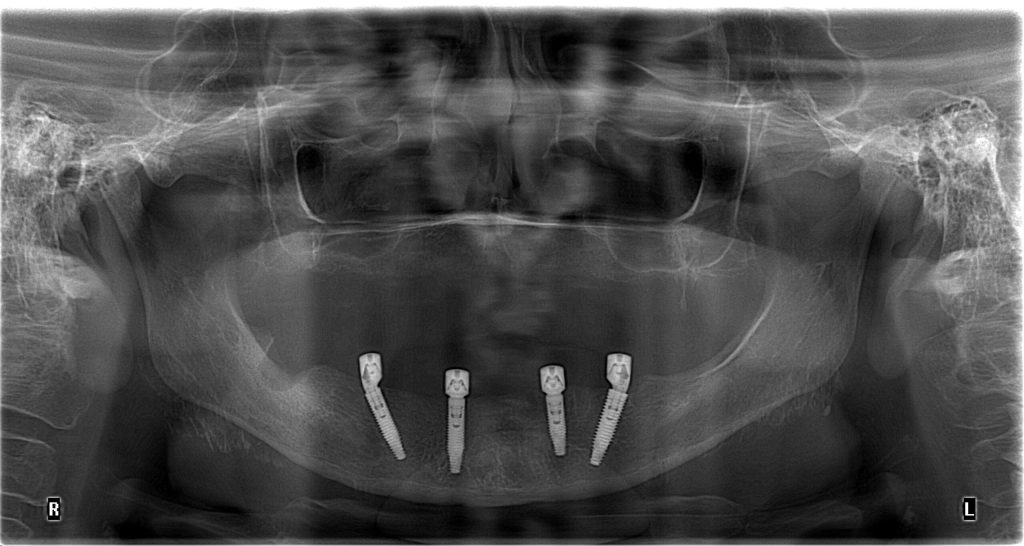

El Centro Radiológico Diagnóstico Oral 3D, es una empresa antioqueña que ofrece a sus pacientes desde el año 2009, tecnología de vanguardia en radiografías tridimensionales con calidad fotográfica. Las posibilidades para mejorar la eficacia en los diagnósticos bucales son evidentes, también lo son las posibilidades de manipulación de imagen. El sistema de imágenes en 3D ofrece detalles sin precedentes, convirtiéndola en la opción idónea para la mayoría de aplicaciones odontológicas, incluyendo implantes, tratamiento de conductos, ortodoncia, odontopediatría, periodoncia y cirugía

El mayor beneficiado con el uso de esta tecnología es el paciente, el cual podrá ser evaluado en todas sus dimensiones con una baja dosis de radiación, con un costo accesible y sin contaminar  el medio ambiente. Dependiendo de la necesidad del paciente, hay varios tipos de tomografías y los especialistas en el área odontológica hacen uso de ellas según su especialidad.

Implantología dental